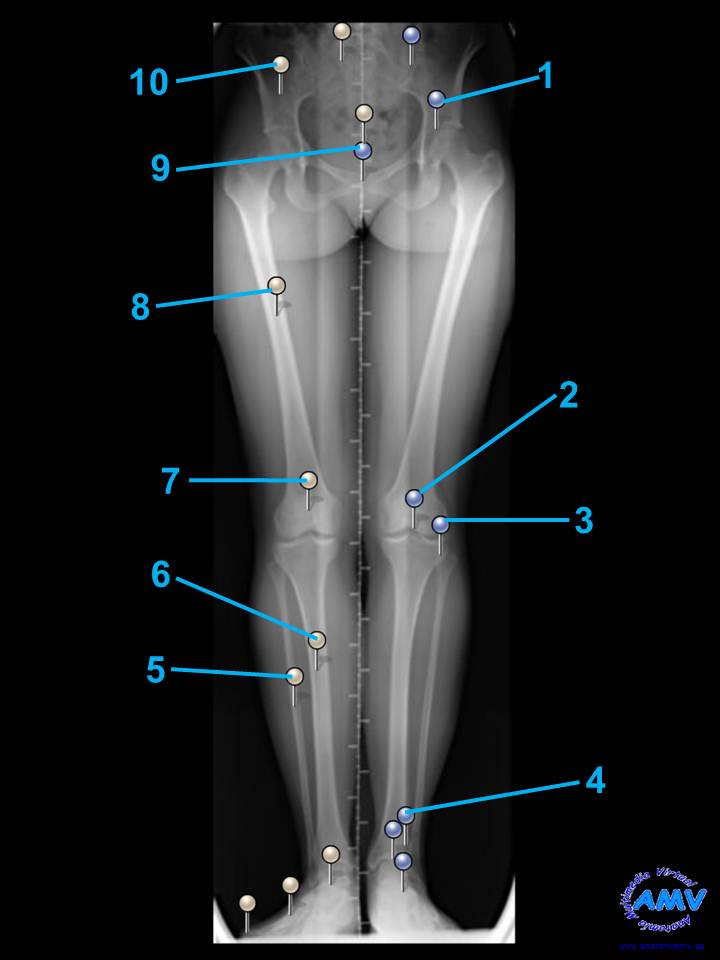

rx_mi_01.jpgIndique que estructura se señala con el número correspondiente:

El nº 1 señala .

El nº 2 señala .

El nº 3 señala .

El nº 4 señala .

El nº 5 señala .

El nº 6 señala .

El nº 7 señala .

El nº 8 señala .

El nº 9 señala .

El nº 10 señala .